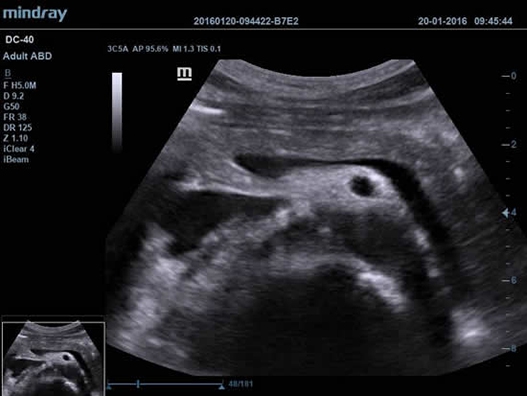

Mindray DC-40 - передовая УЗ-станция с выдающимися возможностями в области медицинской диагностики. Компания Mindray разработала это устройство с учетом высоких требований врачей к качеству изображения и быстродействию. DC-40 обеспечивает высокое качество изображения и точность диагностики, что является необходимым в повседневной практике врачей. Технологии, применяемые в этом устройстве, позволяют получать четкое и детализированное изображение.

Технологии iBeam, iClear и iScape, применяемые в DC-40, позволяют получать объемные изображения высокого качества без помех и зернистости в зоне сигнала. Панорамная визуализация с расширенным обзором анатомических структур решает проблемы сложных диагнозов, которые ранее создавали значительные трудности в ультразвуковой диагностике.

УЗИ-аппарат DC-40 - это передовое медицинское оборудование, которое на протяжении многих лет поможет решать проблемы ваших пациентов, предоставляя готовые и точные диагнозы, выявляя даже самые серьезные патологии на ранних стадиях развития.

• Shared Service Package - предустановленные параметры, аннотации, маркеры, программы измерений для абдоминальных исследований, акушерства, гинекологии, кардиологии, ангиологии, исследований малых органов, урологии, педиатрии, неотложной медицины;